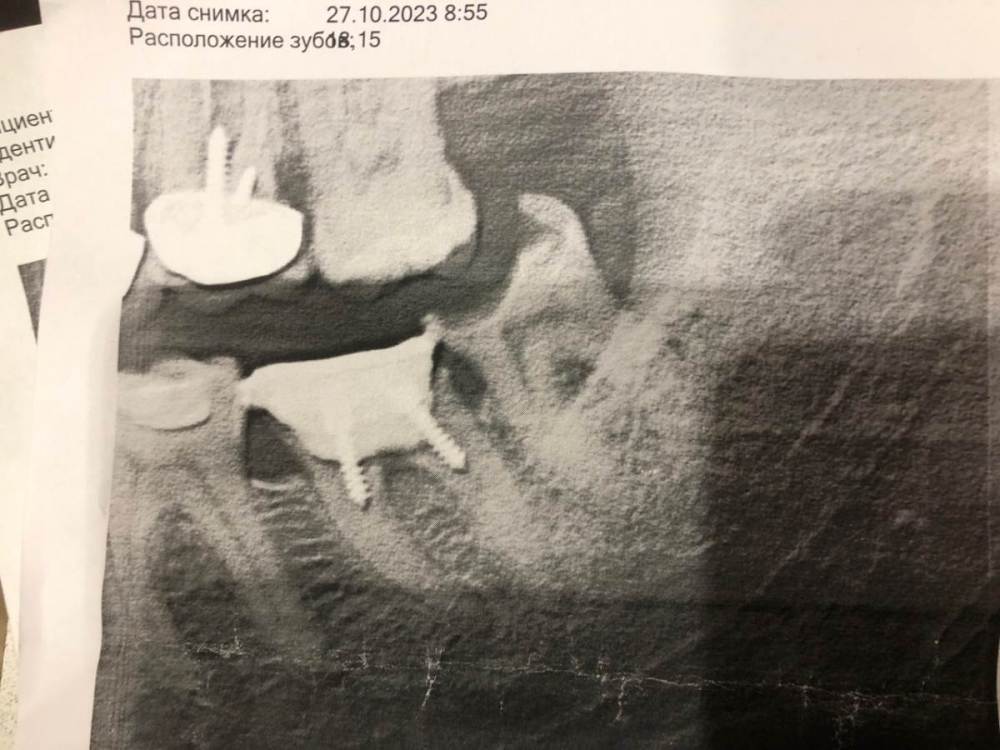

denisss88 Опубликовано 30 октября, 2023 Поделиться Опубликовано 30 октября, 2023 (изменено) Здравствуйте! Откололась пломба на левой 8ке, пошел удалять. Но хирург сказала, что лучше мне его спасать, так как с 7кой проблемы, типа коронку на нее не поставишь уже (права или нет?) И по ее мнению, 8 надо оставить для моста в будущем. Есть 2 снимка с разницей в 3 года, деградации вроде не видно Изменено 30 октября, 2023 пользователем denisss88 Ссылка на комментарий